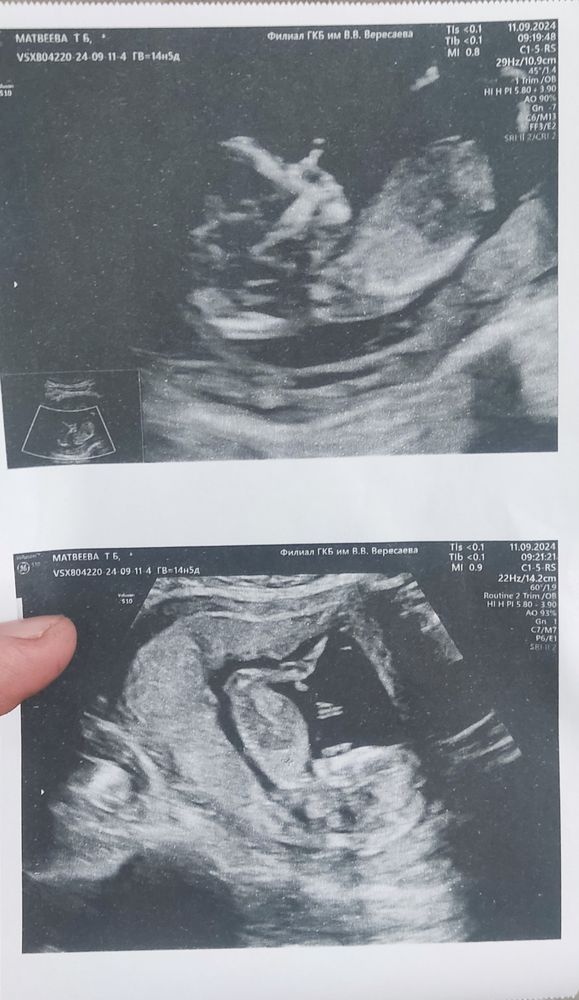

Здравствуйте, ходила сегодня на первый скрининг. Срок 12 недель и 1 день. Врач ничего не сказала , просто дала фото и отправила сдать кровь. Может вы что нибудь скажете , все ли нормально?

Если ничего не сказала, то всё хорошо. А по фотографии вам никогда никто ничего не скажет,так как узистф смотрят размеры не визуально, а измеряют в программе.